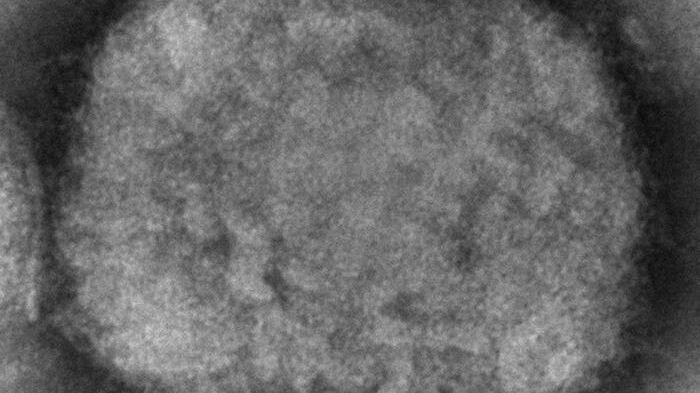

Italia ha contabilizado tres casos confirmados de viruela del mono, después de que este jueves se notificase el primer contagio en un joven procedente de las islas Canarias, en España, informaron hoy fuentes sanitarias.

El Servicio de Vigilancia de Enfermedades Infecciosas del Lacio, la región de Roma, confirmó hoy que los otros dos casos que se estaban estudiando también han dado positivo y habían tenido contacto con el llamado paciente cero que se confirmó este jueves y que había pasado unos días en las islas Canarias.